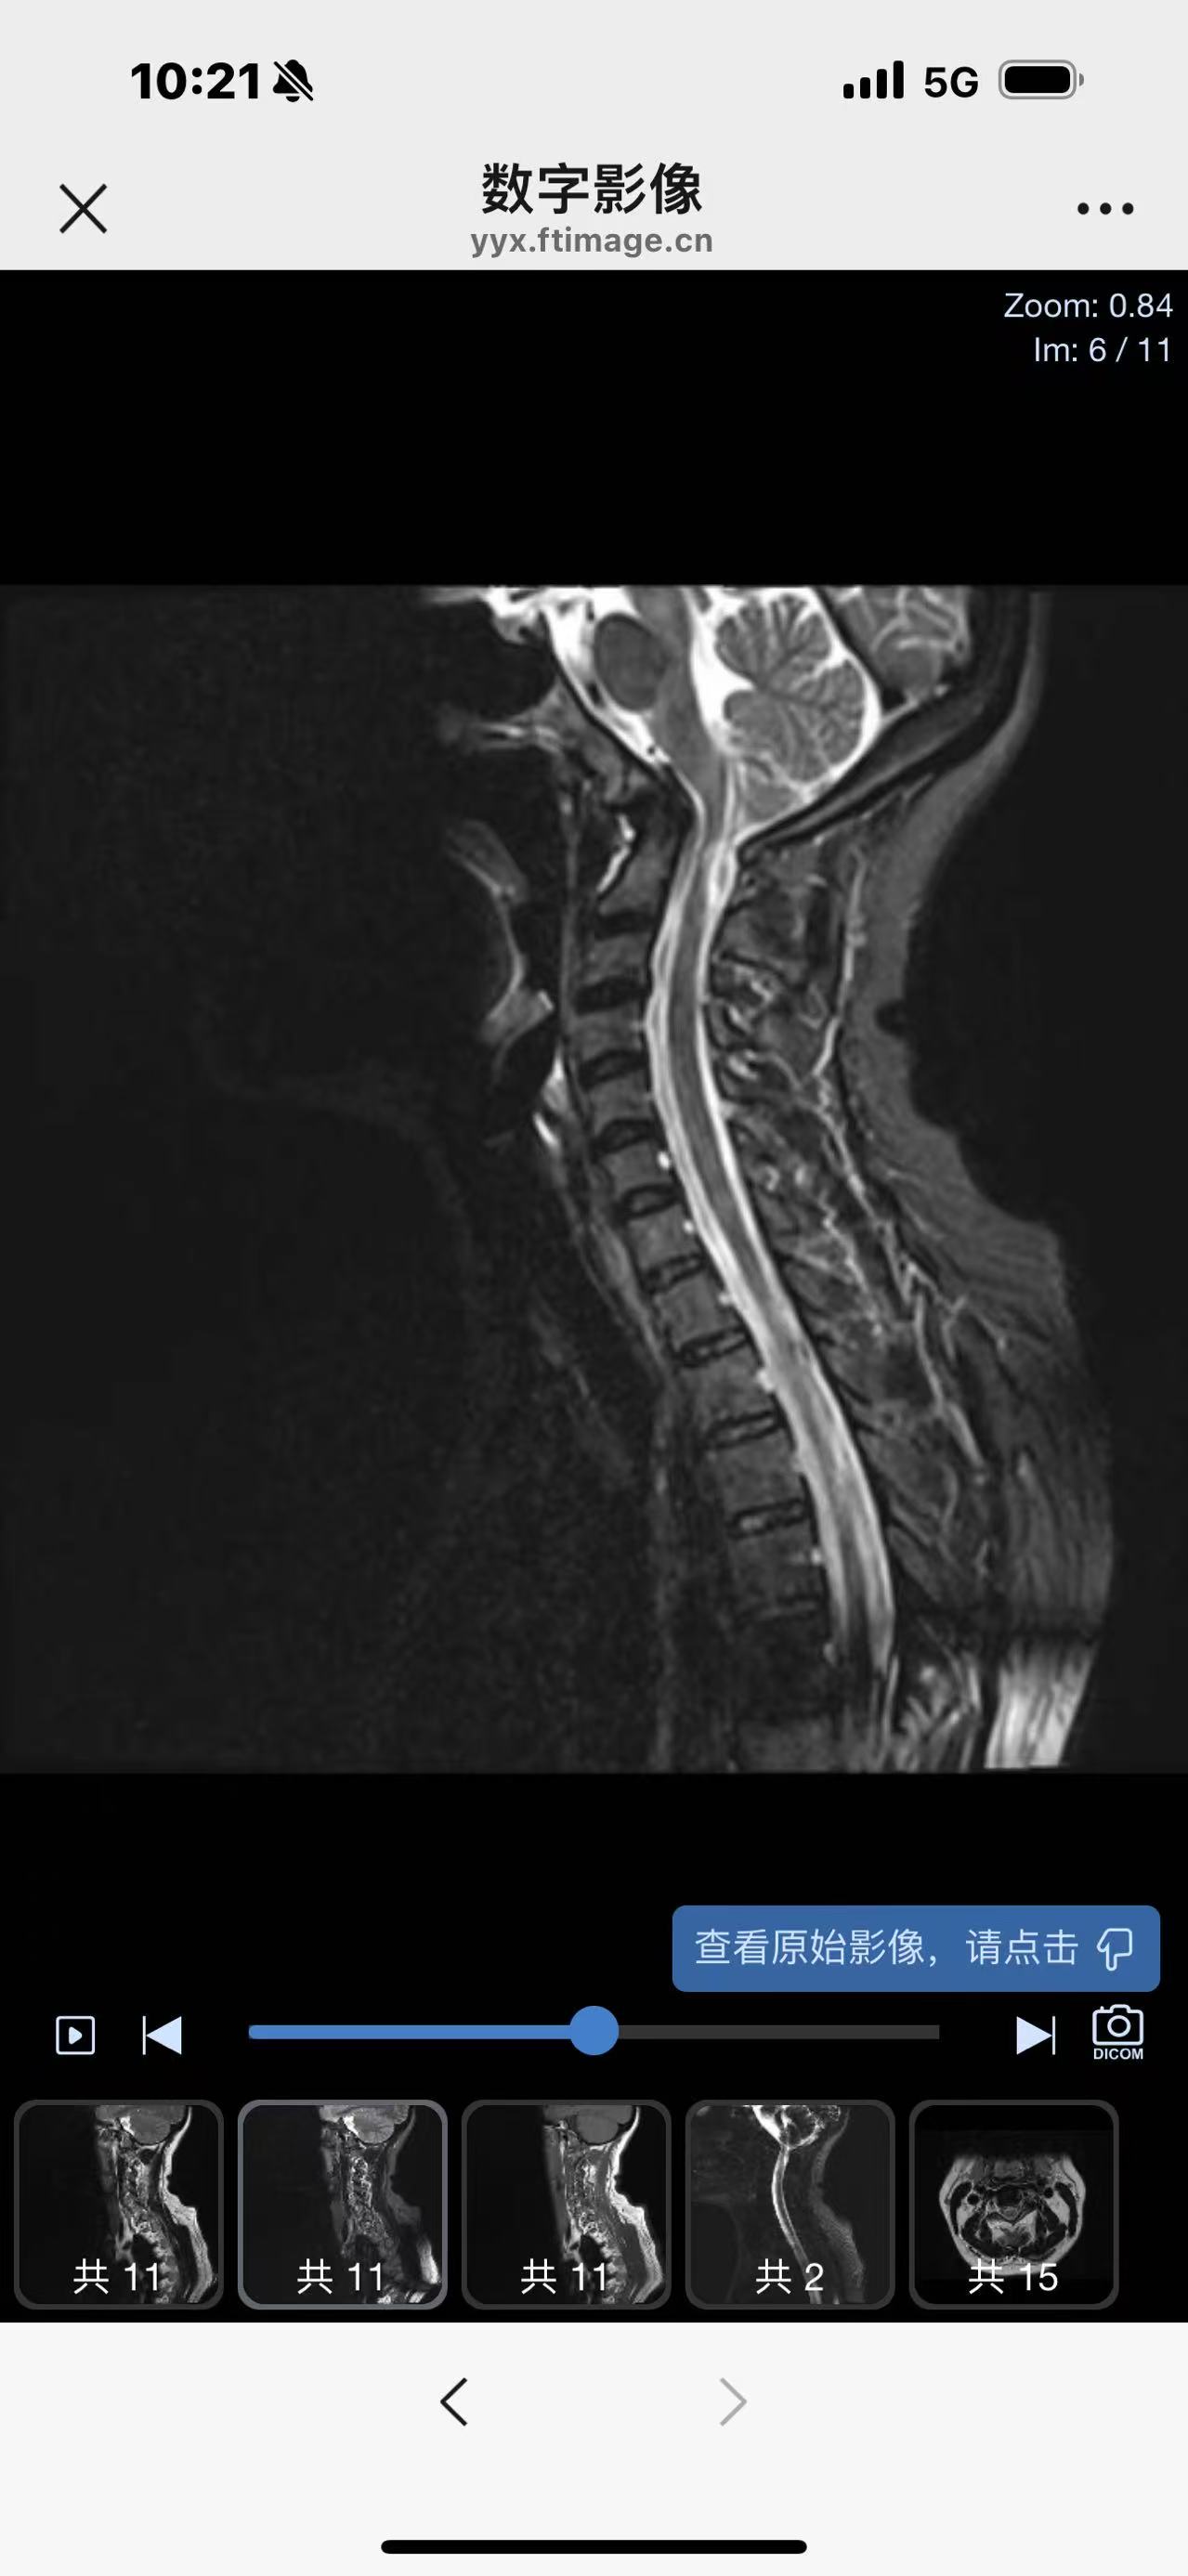

• 诊断:寰枢椎脱位

• 影像:

• 术后影像: